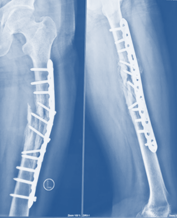

All essential investigations were done and found within normal range. Three (3) days after trauma the fracture was fixed by Dynamic Compression Plate (DCP) with Minimally Invasive Plate Osteo-synthesis (MIPO) procedure. Post-operative radiograph ensured bony fragments and plate ware in potions with maintaining well alignment with minimal fracture gap between fragments (Figure 1).

Figure 1 ThreePost-operative x-ray after Plate Osteo-synthesis.

The patient`s fracture was fixed by Broad Dynamic Compression Plate (DCP) with Minimally Invasive Plate Osteo-synthesis (MIPO) procedure three (3) days after trauma. Post-operative radiograph ensured bony fragments and plate was in position, maintaining well alignment with minimal fracture gap between fragments (Figure 1).